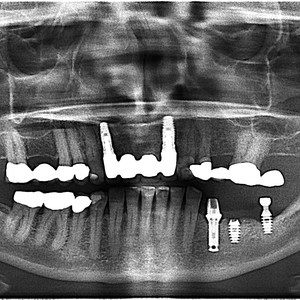

A panoramic radiograph is a panoramic scanning dental X-ray of the upper and lower jaw. It shows a two-dimensional view of a half-circle from ear to ear.

The X-rays use small amounts of radiation. Panoramic X-rays show a broad view of the jaws, teeth, sinuses, nasal area, and temporomandibular (jaw) joints. These X-rays show problems such as impacted teeth, bone abnormalities, cysts, solid growths (tumors), infections, and fractures